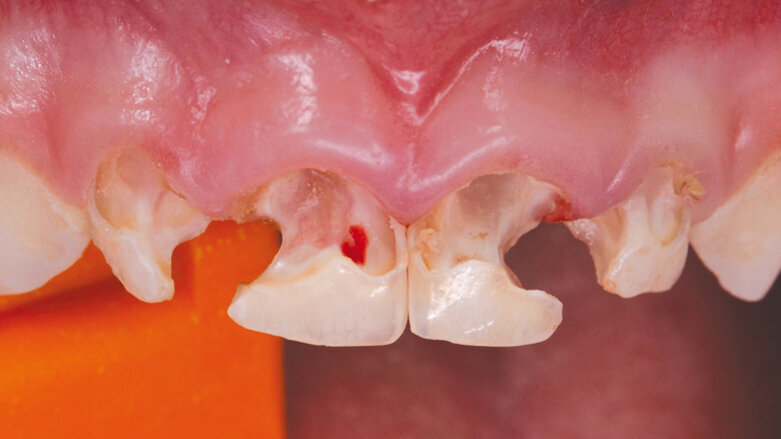

Druhá etapa zahrnovala ošetření horních a dolních řezáků a špičáků. Horní řezáky byly již natolik poškozené (obr. 1), že nebylo možné je rekonstruovat pouze výplněmi, ale bylo třeba ošetřit je korunkami. Proto si dětská zubní lékařka přizvala k tomuto zákroku protetika.

Ošetření bylo zahájeno exkavací kazu horních řezáků, při níž došlo k perforaci do krvácející dřeně zubu 51 a k otevření již po nekróze prázdné dřeňové dutiny zubu 61. Zuby 52, 62 zůstaly vitální (obr. 2). Dětskou zubní lékařkou bylo provedeno endodontické ošetření zubů 51 a 61. Kořenové kanálky byly ručně jemně opracovány, vydesinfikovány 1% chlornanem sodným a zaplněny resorbovatelným materiálem na bázi kalciumhydroxidu s iodofomem (Vitapex). Kořenová výplň byla překryta pod cementosklovinnou hranicí tenkou vrstvou skloionomerního cementu (Fuji IX extra). Zbylé zubní tkáně byly pak protetikem adhezivně připraveny self-etch adhezivem G-aenial (GC), dostavěny do tvaru pahýlů bulkfill kompozitem SDR (Dentsply). Dále byly zuby napreparovány standardní schůdkovou preparací na korunky a opticky naskenovány do CERECu (obr. 3). Poté se dětská zubní lékařka pustila do sanace dolního frontálního úseku fotokompozitními výplněmi a protetik se věnoval výrobě korunek.